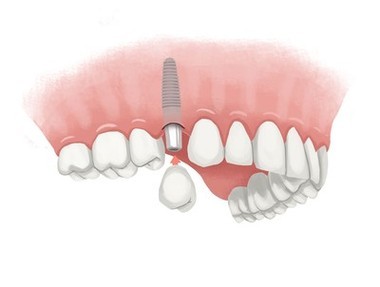

How much does a dental implant cost for one tooth?

The cost of a single-tooth dental implant is estimated to range from $ 3,000 to $ 4,500, according to The New York Times. However, the key to getting the lowest possible cost is to check with a trusted dental implant specialist.

So, is dental implant surgery worth all the problems? Thanks to their durability, appearance and functionality, dental implants are probably the best option to replace missing teeth, providing you with a long-term option that can last for the rest of your life.